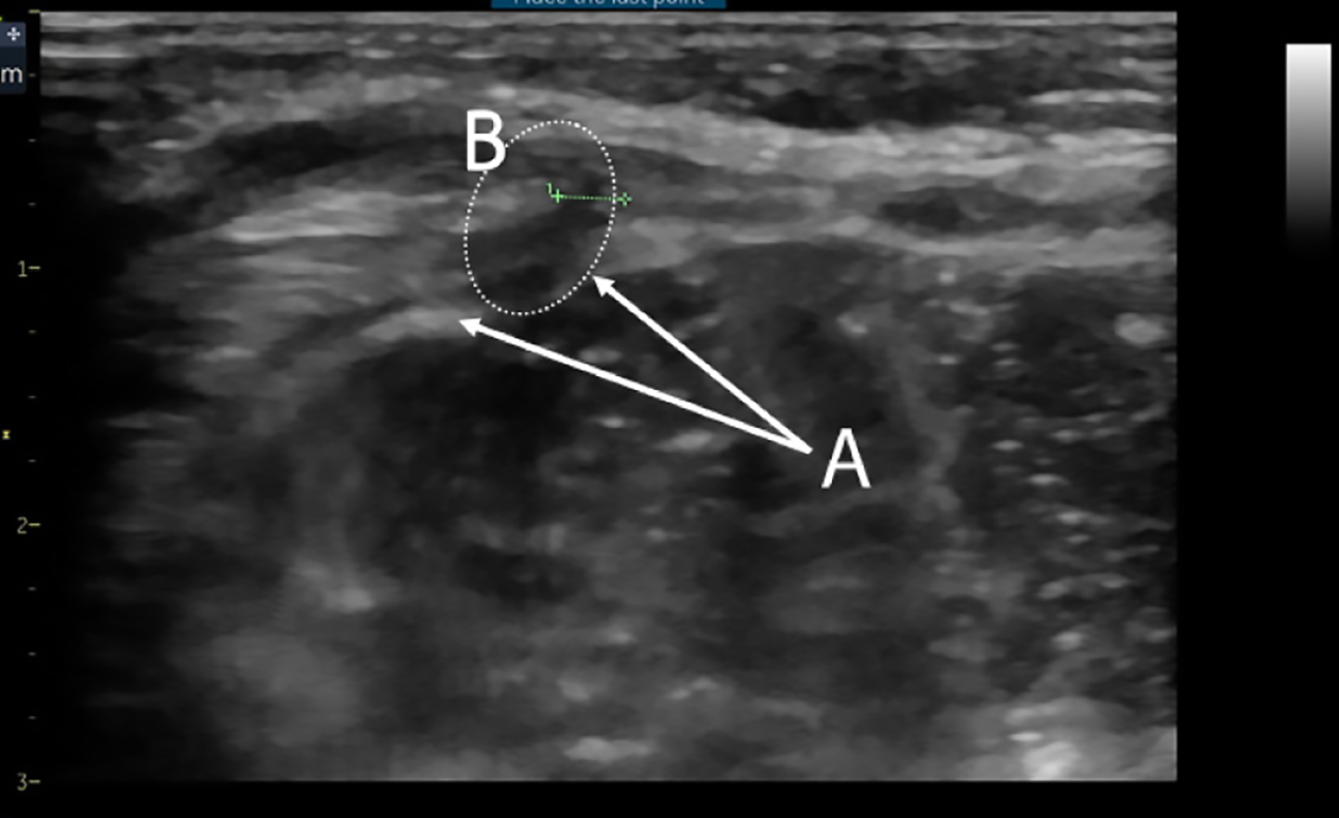

Figure 5 Ultrasound image of the area of interest in the absence of hernia protrusion during examination.

A: Edges of the transverse fascia defect; B: Zone of muscle layer hypoechogenicity.